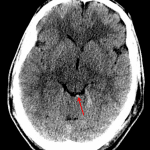

- Small acute intraparenchymal hematoma in the inferomedial left frontal lobe with mild surrounding vasogenic edema

Small acute intraparenchymal hematoma in the inferomedial left frontal lobe measuring approximately 7 by 3 by 7 mm with mild surrounding vasogenic edema. No significant associated mass effect or evidence of herniation.